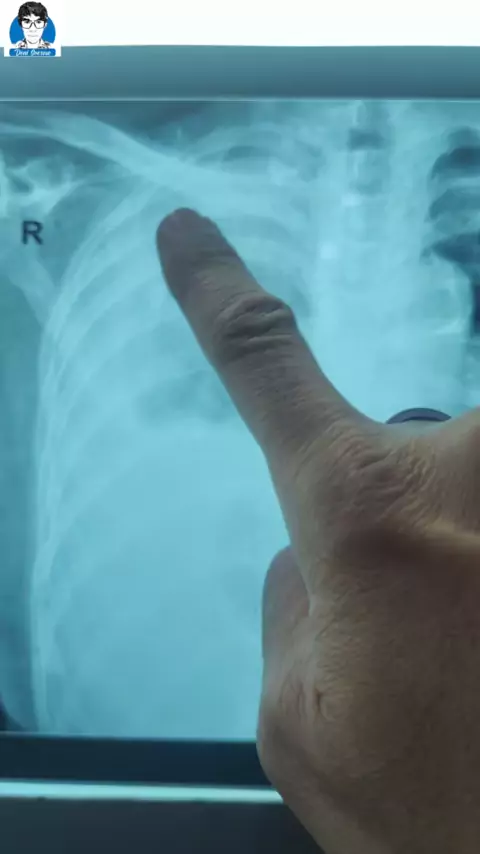

paru kanan ada cairan dan paru Kiri ada udara, diagnosa: effusi pleura kanan ec susp TB Paru+ Partial pneumothorax sinistra#pneumotoraks#punksipleura#pneumothorax#effusipleura#pleuraleffusion#dokterviral#spesialisparu#spesialisparumedan#dokterparu#viralvideo゚viral##viral#